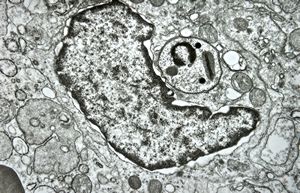

M, 62y. | mitosis … angiomatous tumor, v.s. Kaposi sarcoma